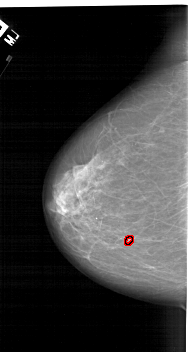

A_1124_1.RIGHT_CC

RIGHT_CC LINES 6571 PIXELS_PER_LINE 3571 BITS_PER_PIXEL 12 RESOLUTION 43.5 NON_OVERLAY

FILE: A_1124_1.LEFT_MLO.OVERLAY

TOTAL_ABNORMALITIES 1

ABNORMALITY 1

LESION_TYPE CALCIFICATION TYPE PLEOMORPHIC DISTRIBUTION LINEAR

ASSESSMENT 4

SUBTLETY 1

PATHOLOGY MALIGNANT

TOTAL_OUTLINES 1

BOUNDARY